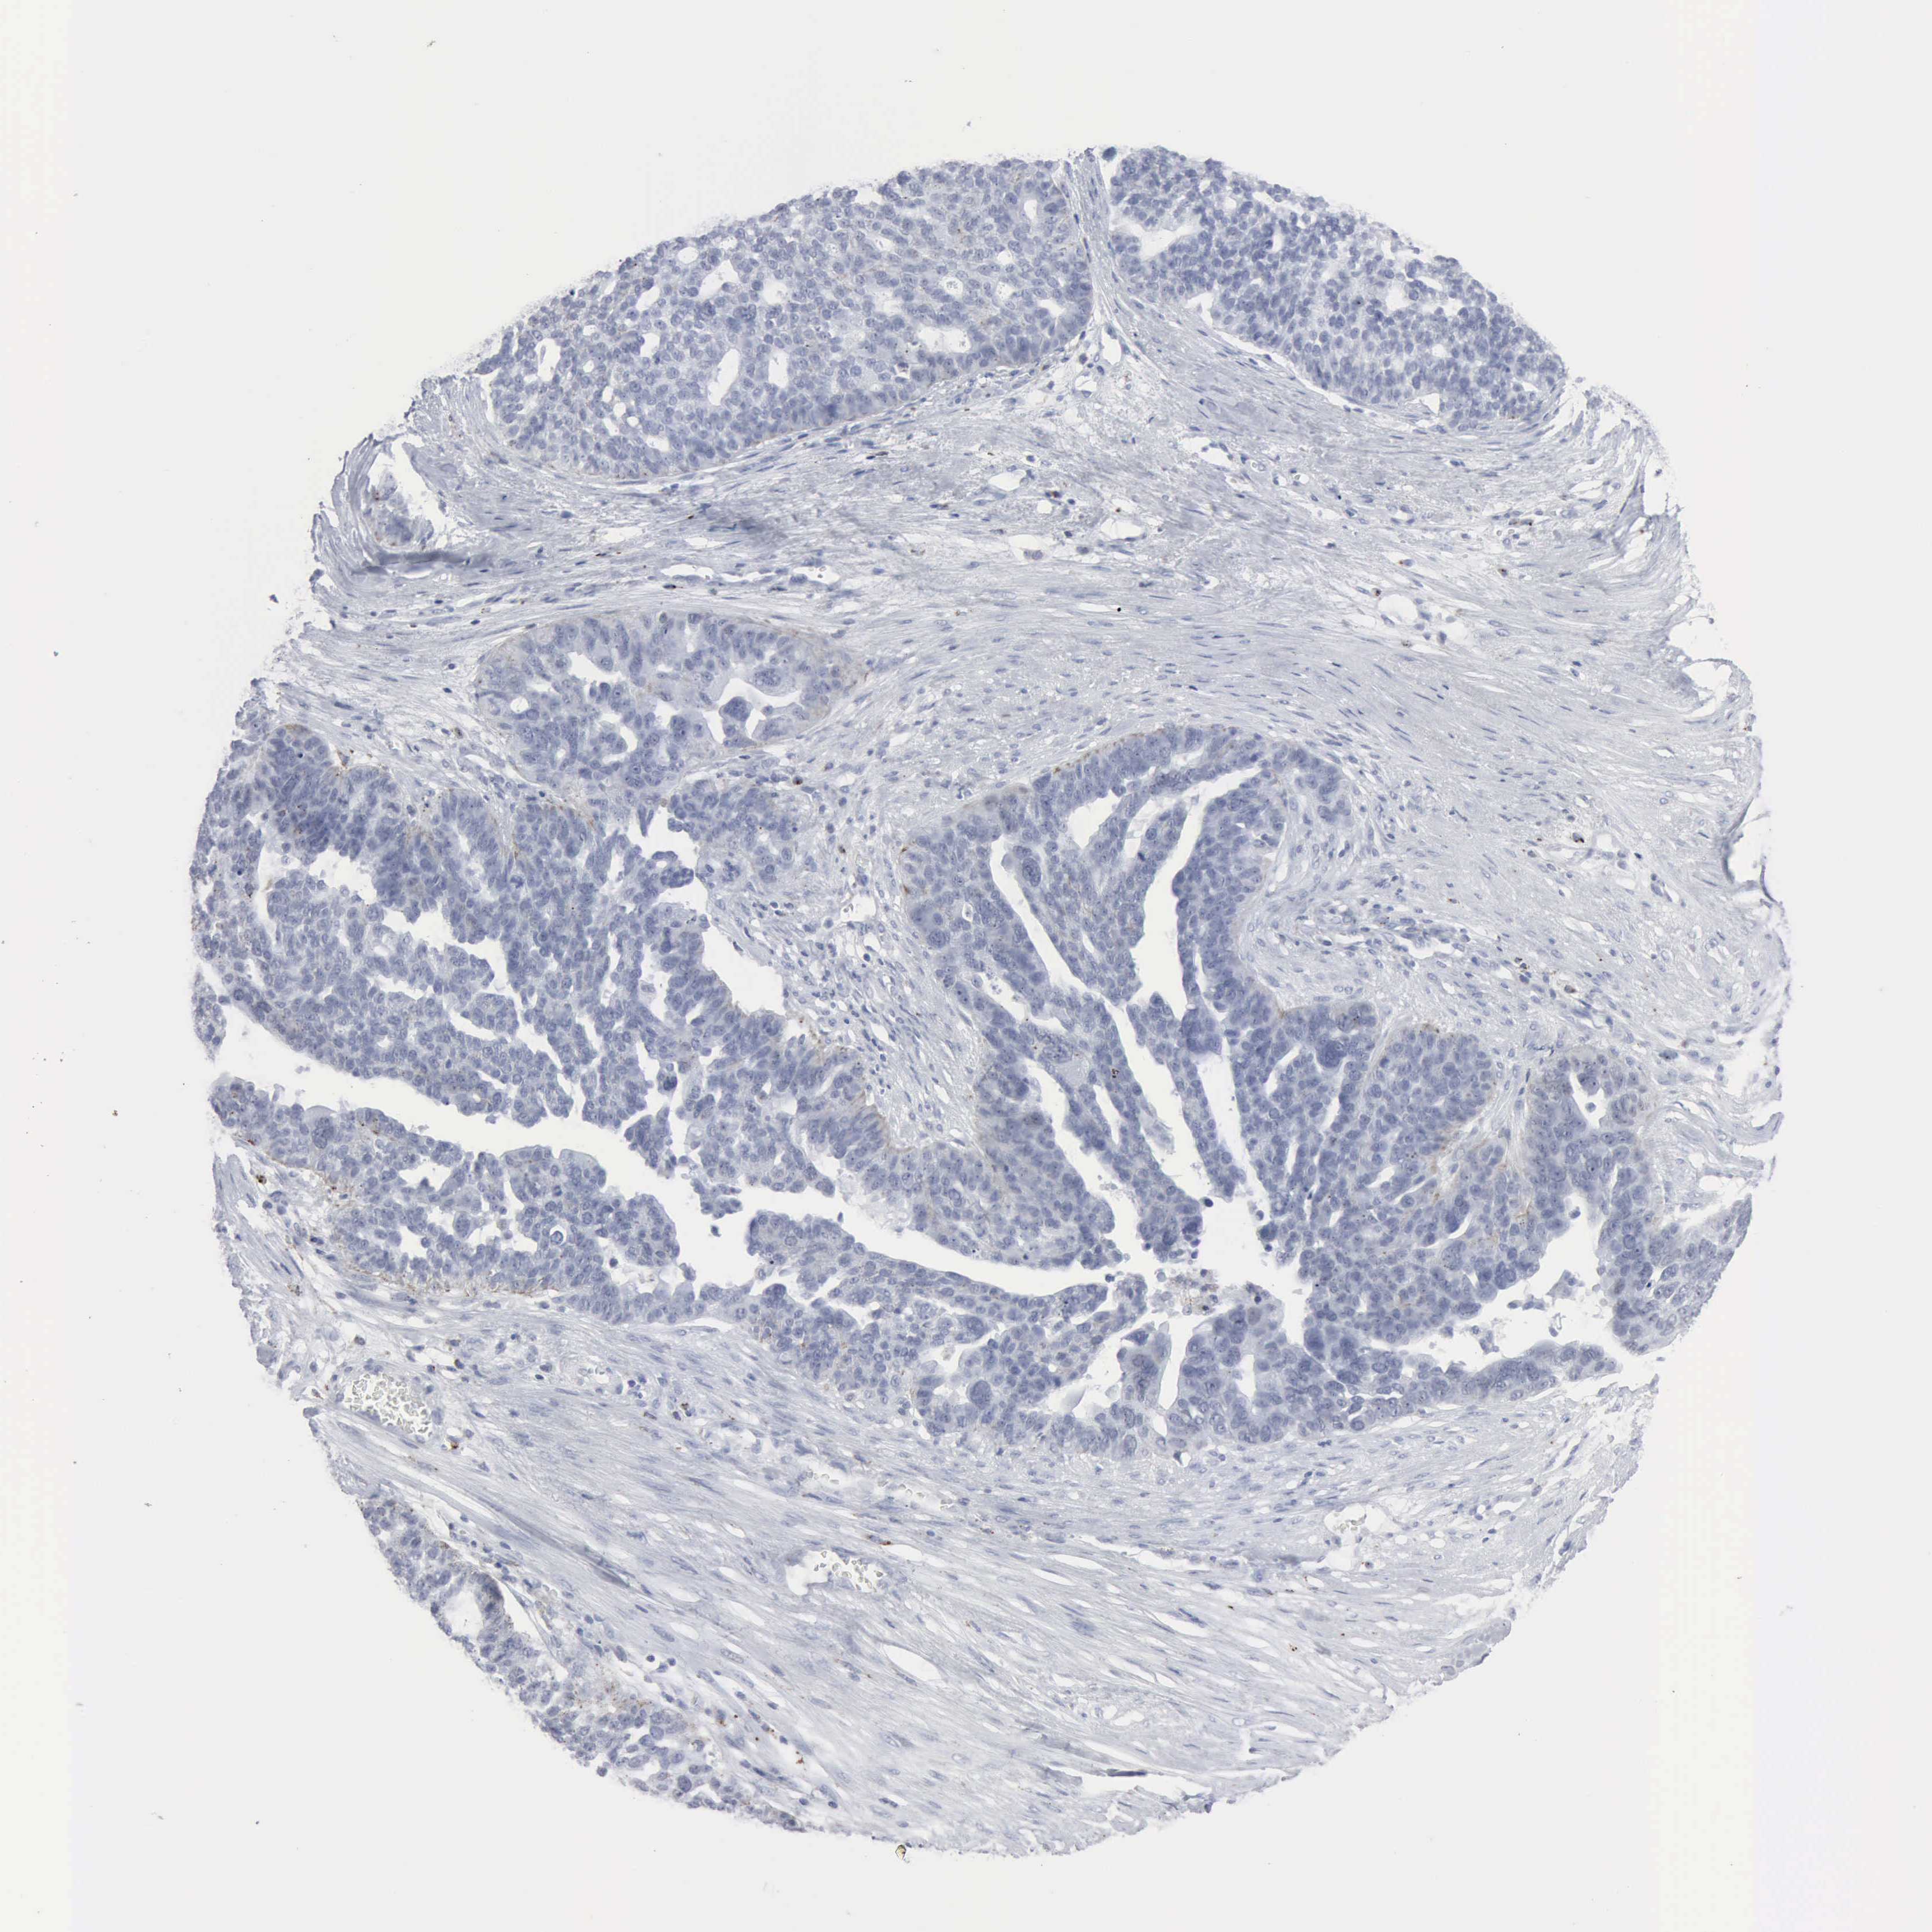

OVARIAN CANCER - Protein expressioni

A mouse-over function shows sample information and annotation data. Click on an image to view it in a full screen mode. Samples can be filtered based on level of antibody staining by selecting one or several of the following categories: high, medium, low and not detected. The assay and annotation is described here.

Note that samples used for immunohistochemistry by the Human Protein Atlas do not correspond to samples in the TCGA dataset.

Antibody stainingi

Antibody staining in the annotated cell types in the current human tissue is reported as not detected, low, medium, or high, based on conventional immunohistochemistry profiling in selected tissues. This score is based on the combination of the staining intensity and fraction of stained cells.

Each image is clickable and will lead to virtual microscopy that enables deeper exploration of all samples and also displays staining intensity scores, fraction scores and subcellular localization as well as patient and tissue information for each sample.

Antibody HPA000237

Antibody HPA000966

Staining

High

Medium

Low

Not detected

Intensity

Strong

Moderate

Weak

Negative

Quantity

>75%

75%-25%

<25%

None

Location

Nuclear

Cytoplasmic/membranous

Cytoplasmic/membranous,nuclear

Cystadenocarcinoma, mucinous, NOS

Carcinoma, endometroid

Cystadenocarcinoma, serous, NOS